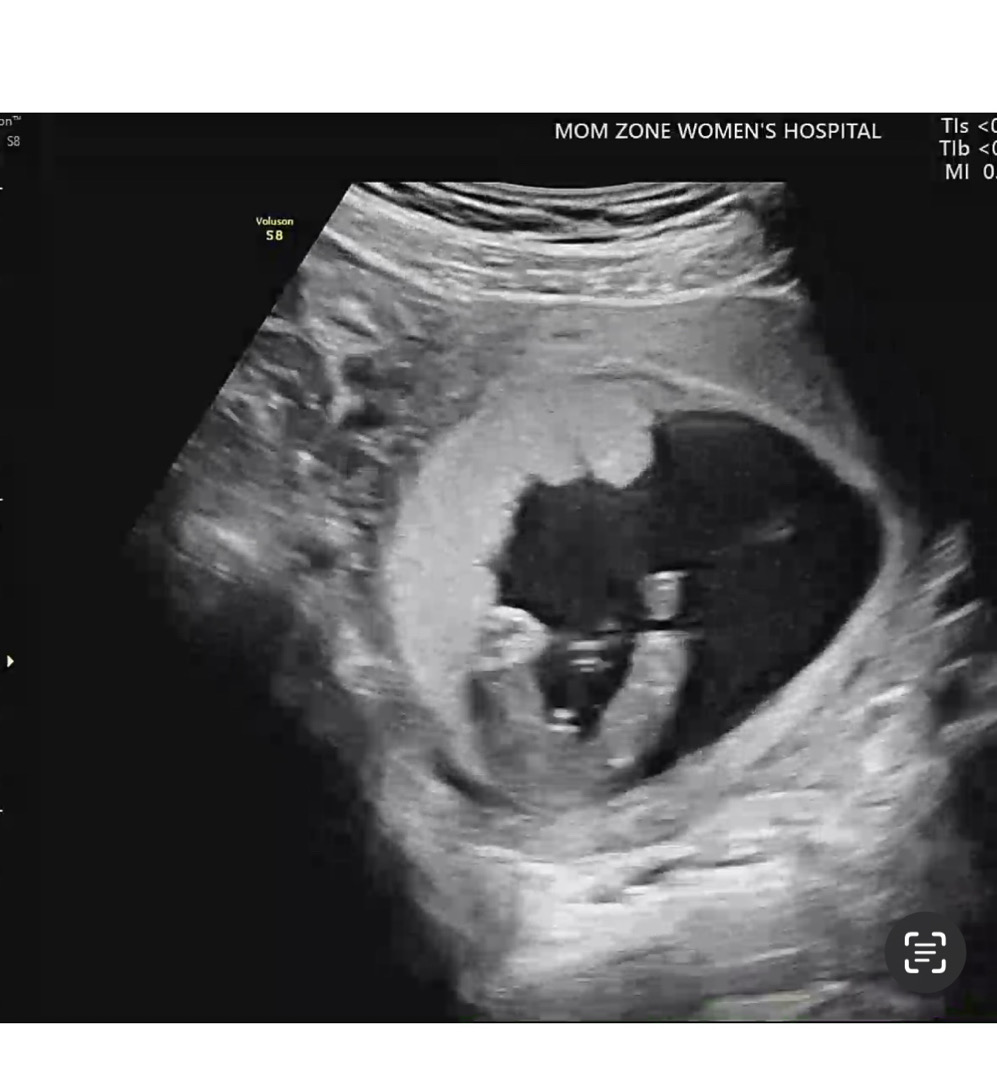

누가봐오 아들이죵?ㅋㅋㅋ

누가봐도 아들이졍? 오늘 15주 입니당

점 세개면 빼박이요 ㅎ

넹ㅎㅎ아들이요!